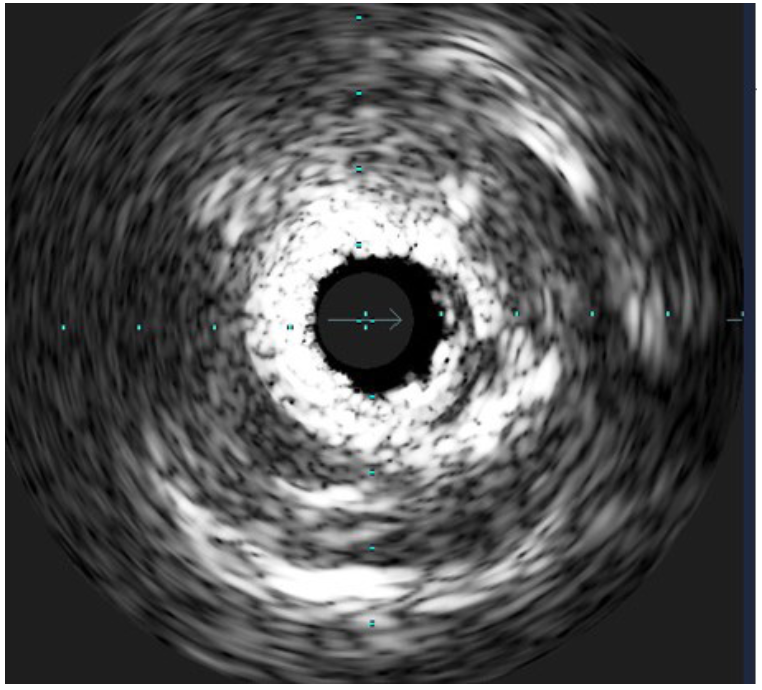

A 67-year-old male presented with non-ST-elevation myocardial infarction (STEMI). Angiography showed severe restenosis within the previously (before 2 years) implanted 2 stents (3 x 24 mm) in the right coronary artery (RCA). Severe calcification was evident angiographically (Figure 1) and after multiple dilations with noncompliant (NC) balloons, the focal underexpansion of the stent remained (Figure 2). This was confirmed by intravascular ultrasound with a minimum stent area (MSA) of 1.98 mm2 (Figure 3). A 3 x 12 mm intravascular lithotripsy (IVL) balloon was used and after the third series of 10 pulses, full expansion of the stent was observed (Figure 4). Postdilation of stenosis with NC and drug-eluting balloons was accompanied by excellent angiographical result with residual stenosis 0%, Thrombolysis in Myocardial Infarction 3 flow, and MSA of 6.4 mm2. The patient was discharged free of symptoms and remains uneventful with no complications. The case demonstrates the feasibility of IVL in acute coronary syndromes related to stent underexpansion due to severe calcification that is refractory to other conventional techniques.